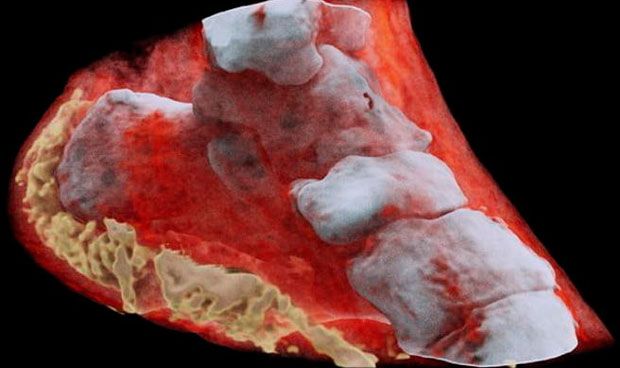

Nueva Zelanda Desarrolla Radiografías A Color Que Serán Útiles Para Estudiar El Cáncer

STAFF/@michangoonga Una empresa de Nueva Zelanda ha desarrollado un nuevo tipo de escáner que permite realizar radiografías en 3D y…